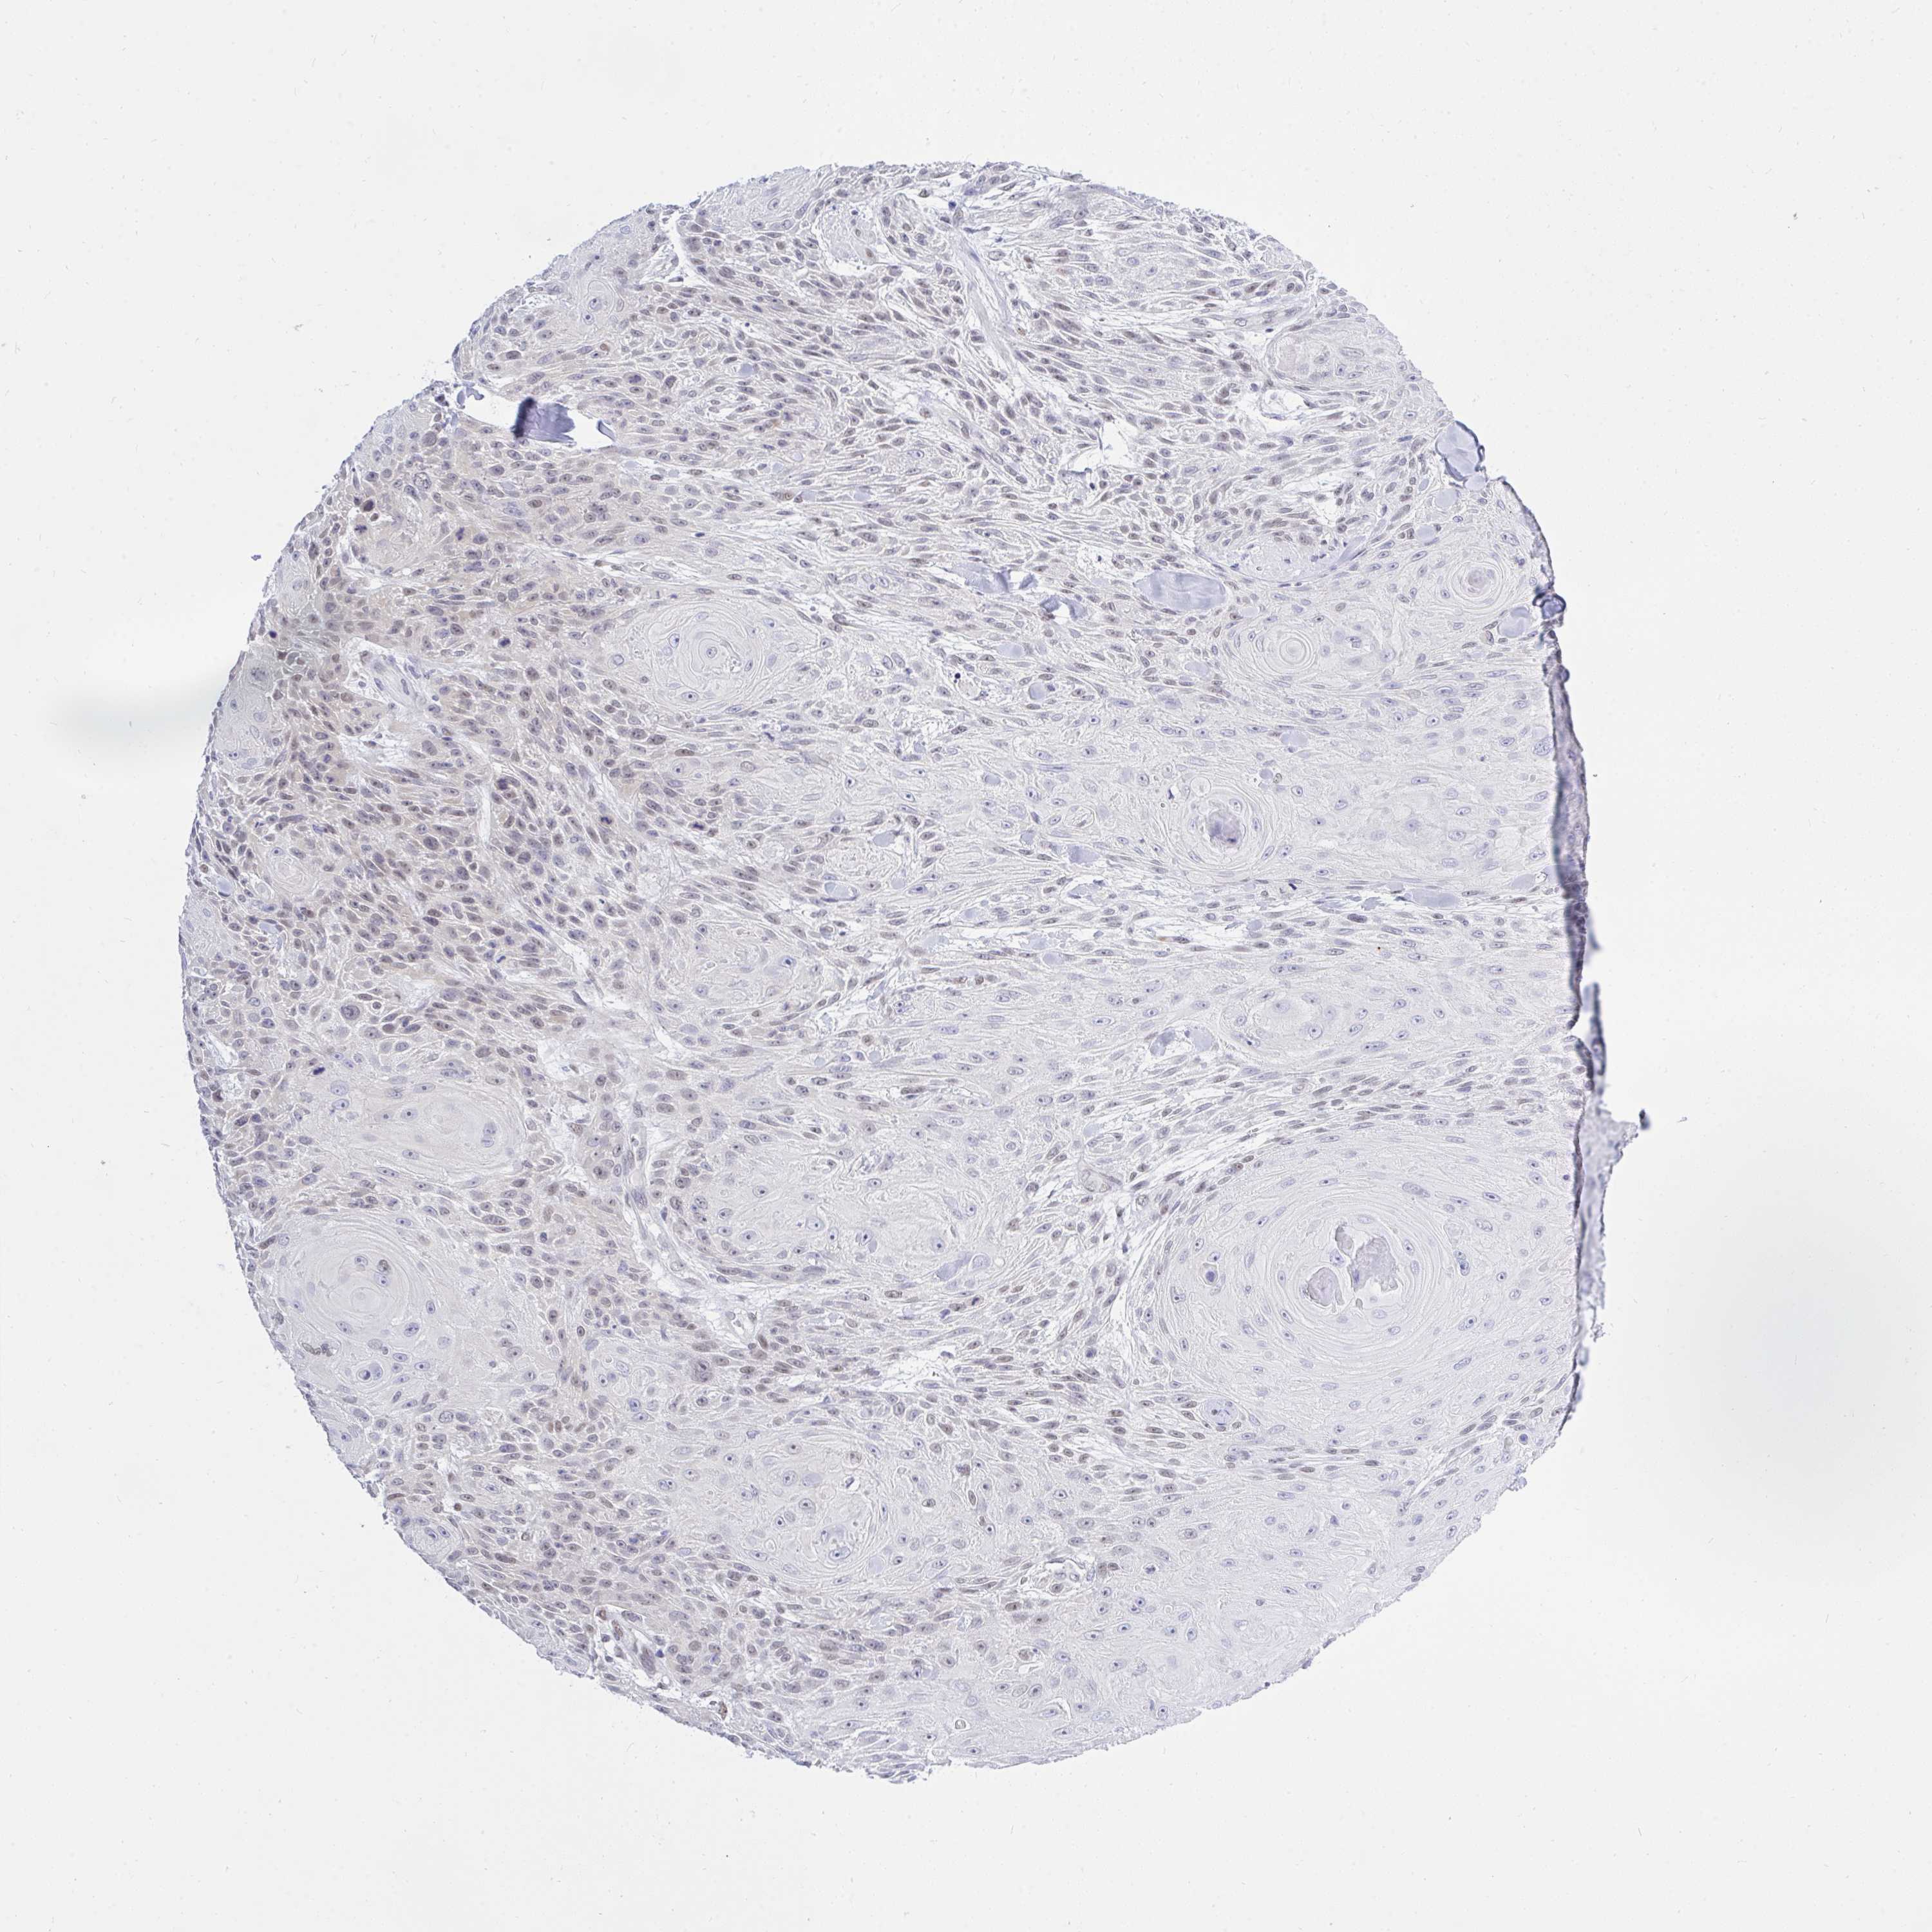

SKIN CANCER - Protein expressioni

A mouse-over function shows sample information and annotation data. Click on an image to view it in a full screen mode. Samples can be filtered based on level of antibody staining by selecting one or several of the following categories: high, medium, low and not detected. The assay and annotation is described here.

Antibody stainingi

Antibody staining in the annotated cell types in the current human tissue is reported as not detected, low, medium, or high, based on conventional immunohistochemistry profiling in selected tissues. This score is based on the combination of the staining intensity and fraction of stained cells.

Each image is clickable and will lead to virtual microscopy that enables deeper exploration of all samples and also displays staining intensity scores, fraction scores and subcellular localization as well as patient and tissue information for each sample.

Antibody CAB025497

Squamous cell carcinoma, NOS